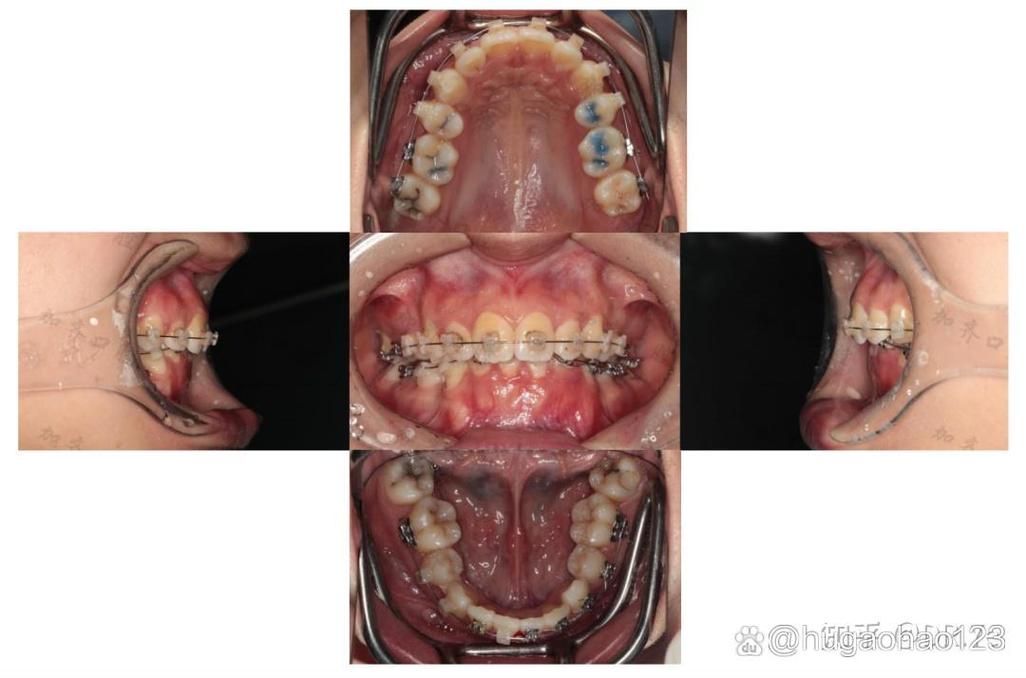

一是咬合功能异常,部分患者治疗后存在咬合干扰,如前牙深覆合、深覆盖未完全纠正,后牙咬合不平衡,导致咀嚼效率下降,严重时可能出现颞下颌关节紊乱(TMD),表现为关节弹响、疼痛、张口受限等,有患者因正畸后后牙咬合过高,前牙无法接触,长期导致关节区肌肉疲劳,甚至出现头痛。

二是牙齿排列与美观问题,最直观的是牙齿排列不整齐,如“扇形”未改善、牙齿扭转未纠正、中线偏斜等;部分患者出现牙龈萎缩、牙根暴露,或因牙槽骨吸收导致牙齿松动,影响美观和口腔健康。

三是口腔健康并发症,正畸过程中若口腔卫生维护不当,易引发龋齿、牙周炎;部分患者因牙齿移动过快或施力不当,导致牙根吸收,表现为牙齿松动、牙冠变短,甚至影响牙齿寿命。

四是治疗效果不稳定,治疗后牙齿复发移位,如原本排齐的牙齿再次拥挤,或矫正后的咬合关系逐渐改变,多与保持器佩戴不当、不良习惯未纠正有关。